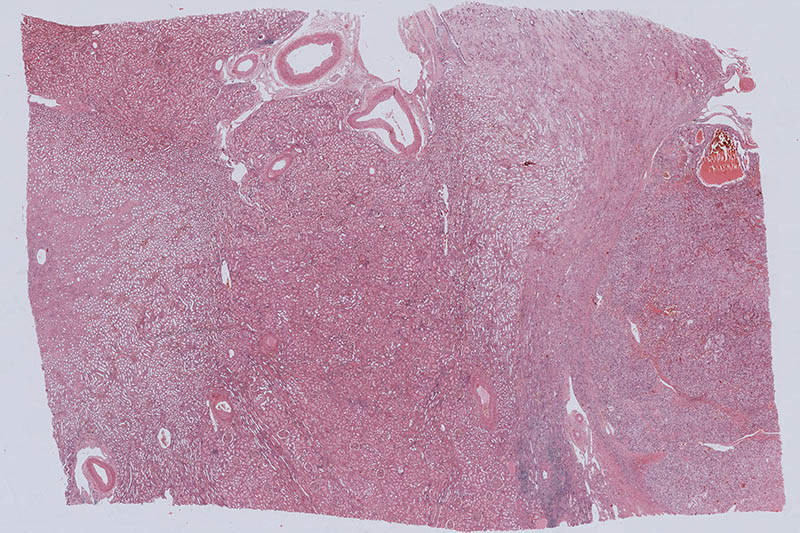

掃描模式 |

明場掃描,熒光掃描 |

功能 |

明場切片掃描

多重?zé)晒馇衅瑨呙?br>

一鍵Z-Stack層掃 |